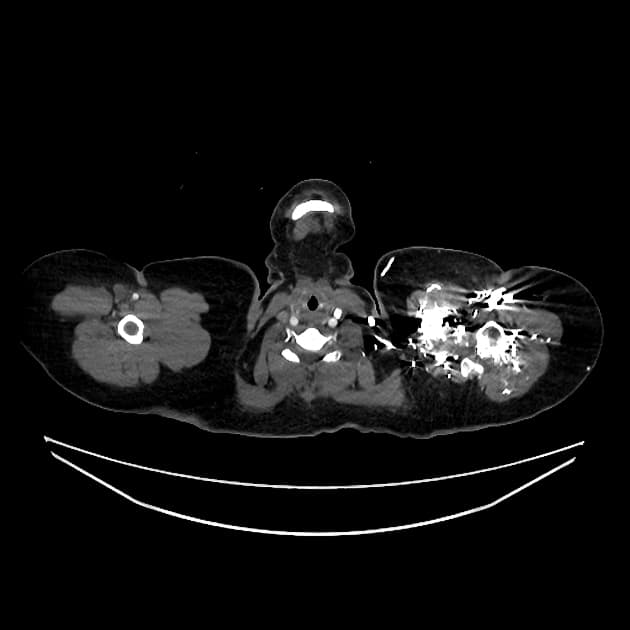

- Phình động mạch chủ lên (ascendant aorta aneurysm) >50 mm.

- Ống động mạch còn ống (patent ductus arteriosus), dạng kéo dài (elongated type), có hình ảnh thuốc cản quang đổ vào thân động mạch phổi giãn vừa (shunt trái sang phải - left to right shunt).

- Nhĩ trái giãn, kèm dày vách liên thuỳ và dày quanh phế quản - mạch máu, phù hợp với phù do tim nhẹ (mild cardiogenic edema).